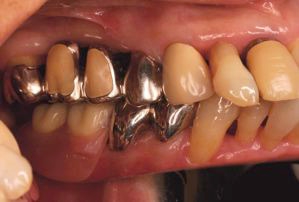

両側5歯症例

両側5歯症例両側5歯症例両側5歯症例 主訴-義歯のバネが壊れて手前の歯が痛んできた。 術前(旧義歯装着、鏡像) 術前(下顎粘膜面、鏡像)術前(下顎粘膜面、鏡像)術前(下顎粘膜面、鏡像) 術前レントゲン術前レントゲン術前レントゲン 術前口腔内(正面観)術前口腔内(正面観)術前口腔内(正面観)

術後(鏡像)術後(鏡像)術後(鏡像) 術後口腔内(正面観)術後口腔内(正面観)術後口腔内(正面観)もう入れ歯は要らなくなりました。 術後レントゲン術後レントゲン術後レントゲン